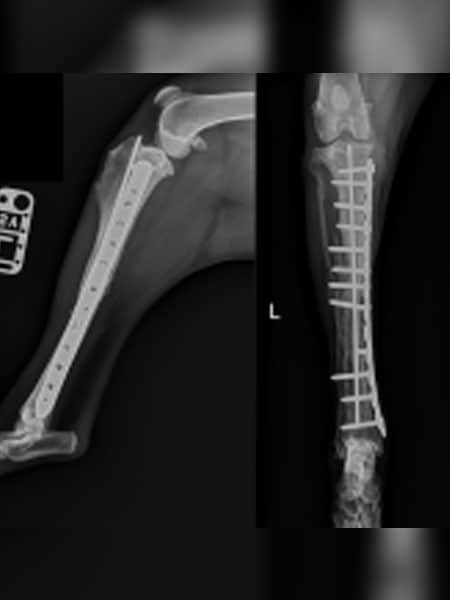

Fracture Repair

We are equipped and skilled to be able to choose the best methods to fix broken bones, including Plates and Screws, External Fixators, Pins and Wires.